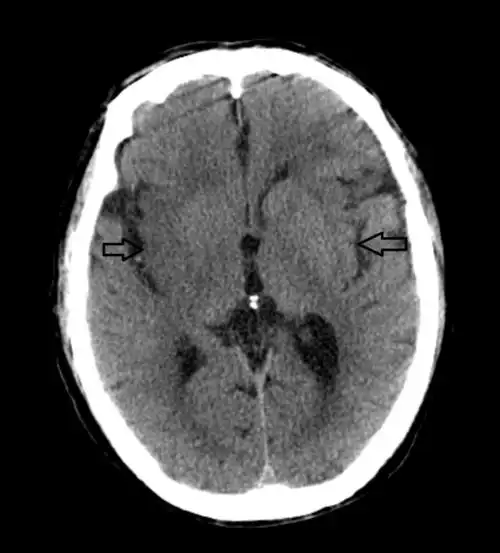

67超急性期大面积脑梗死ct平扫表现